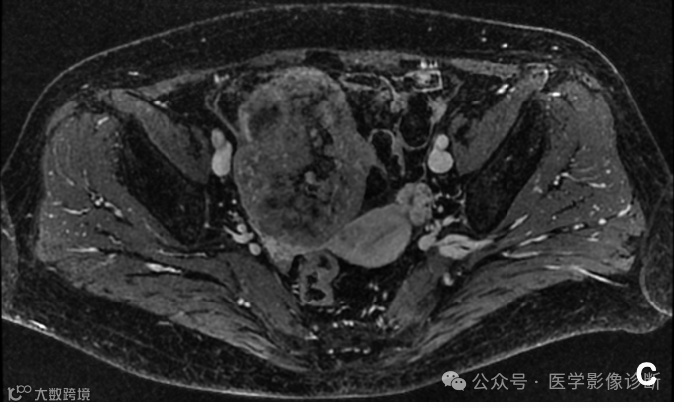

MRI扫描(a - c)显示盆腔肿块,T1WI呈出血样高信号,T2WI/FS内部呈低信号。增强扫描表示非均匀增强。肿块与小肠密切相关,增强MRI矢状面(d)和轴向CT (e)可见肠系膜大血管(箭头)供血,提示肠道原发病变。然而放射科医生受临床卵巢肿瘤的诊断干扰未能明确诊断为小肠间质瘤。